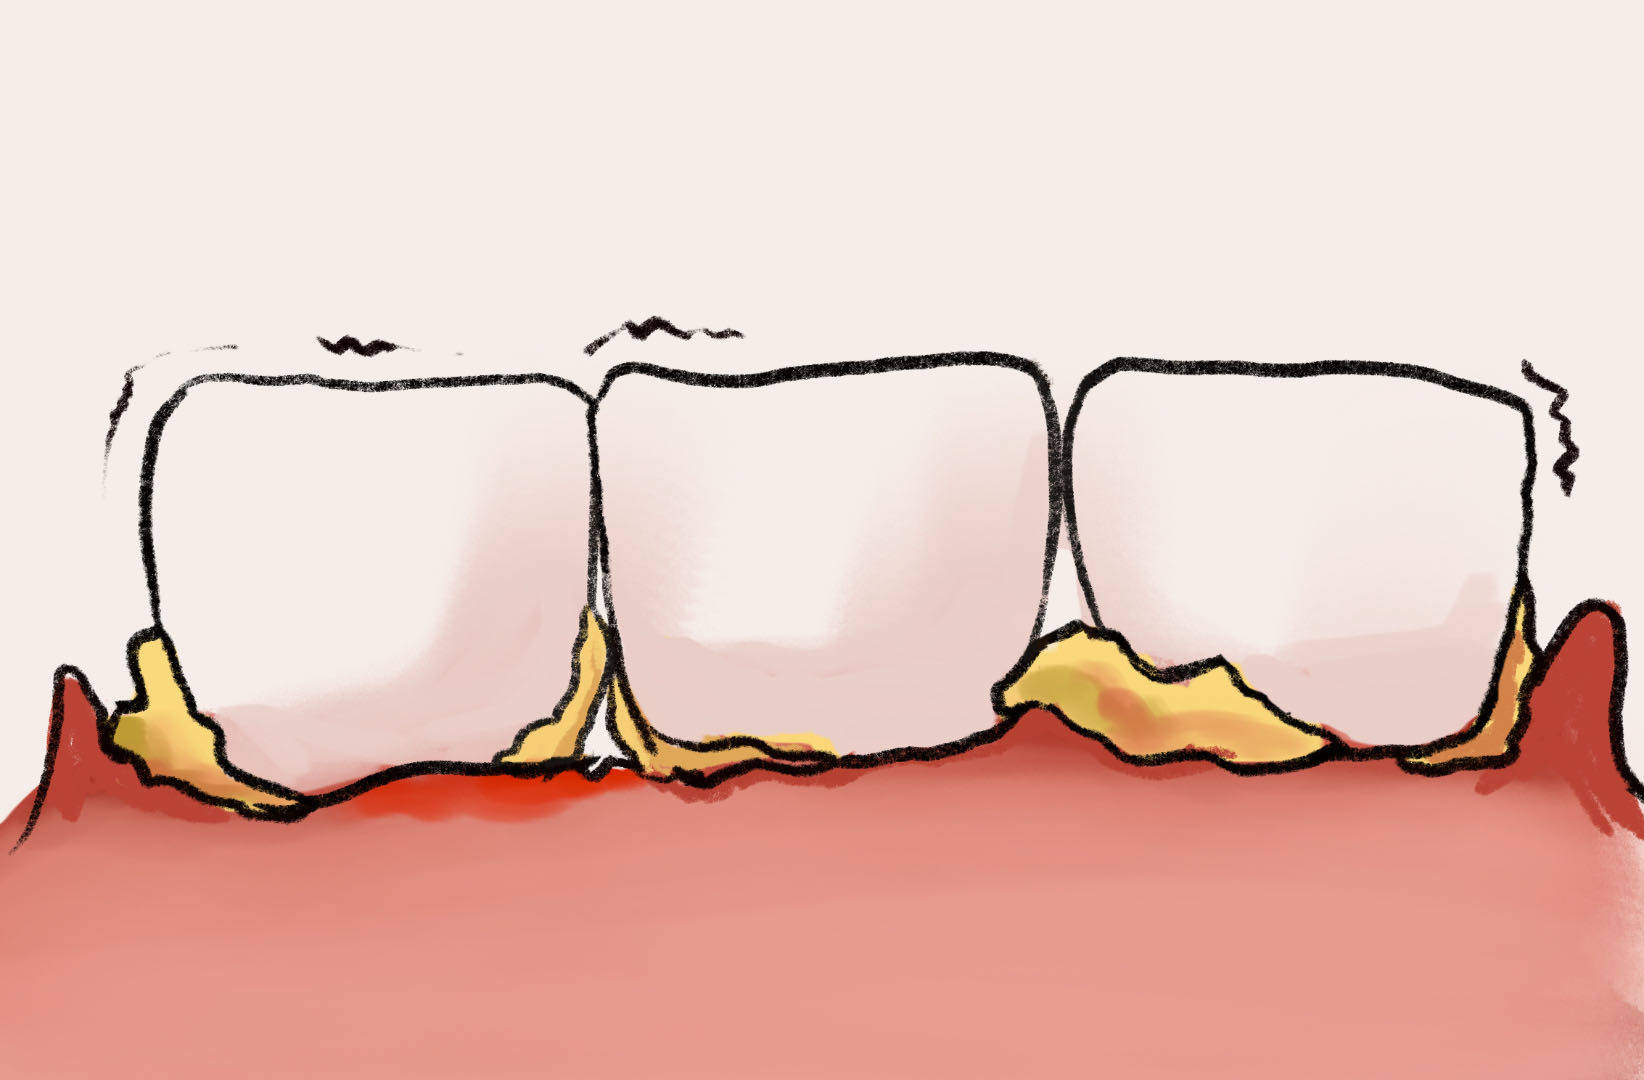

29岁女子牙结石张嘴就尴尬,医生:预防牙结石,做好这些事

牙结石的形成原因及预防方法